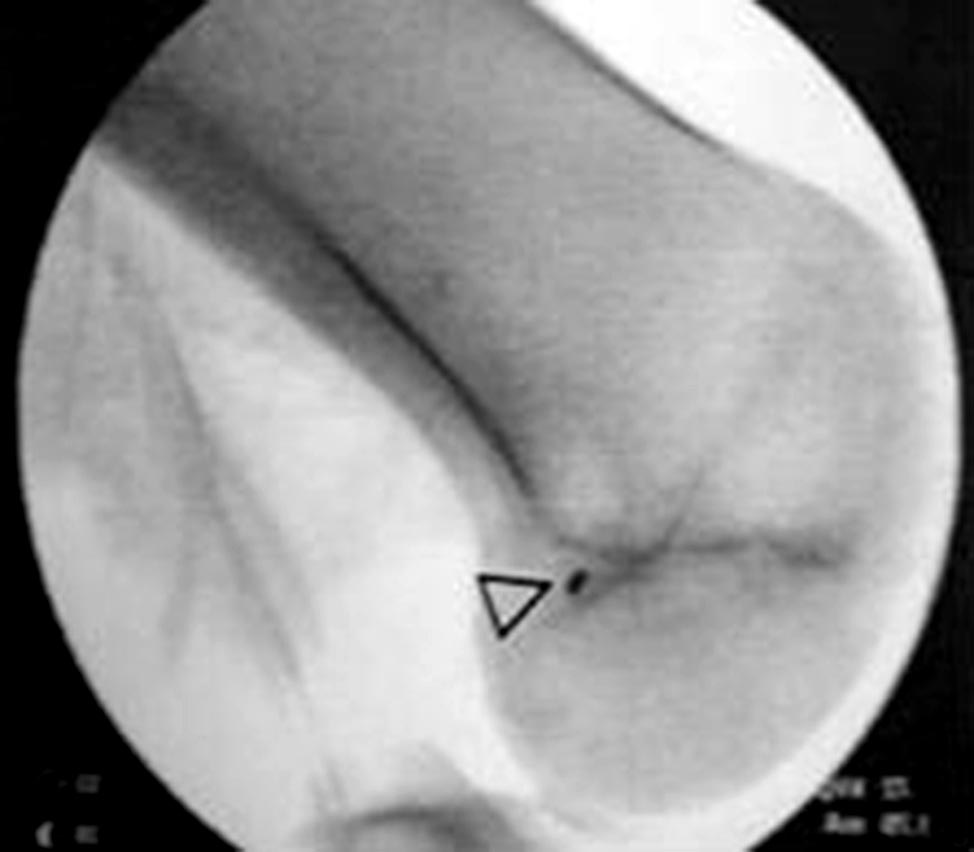

Se realiza la toma de injerto del recto interno mediante una incisión de 1 a 3 cm sobre la inserción tibial de la pata de ganso, para luego disecar el recorrido del tendón con un tenótomo de 5 o 7 mm de diámetro. Si el tendón del recto interno es insuficiente, debemos realizar el mismo procedimiento con el tendón del semitendinoso (Fig. 2). Se realiza una incisión de 3-4 cm sobre el borde medial de la rótula, esqueletizando el mismo en su mitad proximal con electro-bisturí y legra (Fig. 3). Una vez expuesto el borde medial de la rótula, se realizan 2 túneles de 20 a 22 mm de profundidad, con una mecha de 4 mm de diámetro. La dirección de los mismos es ligeramente convergente para el anclaje del injerto. Uno cefálico a 5 mm del borde superior de la rótula y el otro más caudal, aproximadamente 20 mm respecto al túnel mencionado previamente (Fig. 4). Se realiza una nueva incisión de 2 a 3 cm a nivel del epicóndilo medial para realizar el túnel de fijación femoral del injerto. La localización anatómica de éste es más compleja e importante que la rotuliana, ya que si lo realizamos en un lugar incorrecto perjudica la isometría del neo ligamento. El sitio de fijación se encuentra entre el tubérculo del aductor y el epicóndilo medial14 (Fig. 5). La asistencia del intensificador de imágenes para su correcta ubicación es de gran utilidad. La localización radiológica es 1,3 mm anterior a la prolongación de la cortical posterior, 2,5 mm a distal de una perpendicular a la línea de Blumensaat (Fig. 6).

Figura 6: Imagen radioscópica intraoperatoria del sitio de fijación femoral.